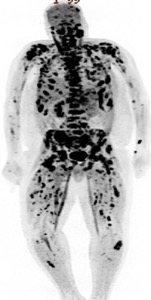

Case Presentation: A 40-year-old male presented to the emergency department with complaints of back pain for 3 weeks. He described the pain as aching and circumferential involving the sternum, right ribs, shoulders, and back. His previous medical history was unremarkable and he never had any prior imaging studies. Plain radiographs of the spine did not show any osseous abnormalities. Because of the patient’s highly elevated alkaline phosphatase (1,051 IU/L), a computed tomography (CT) scan of the chest, abdomen, and pelvis was performed (figure 1). This revealed an enhancing right upper pole renal mass suspicious for renal cell carcinoma with nodal, left adrenal and extensive bony metastasis. In the chest, there were extensive lytic and sclerotic bone metastases. Interventional Radiology performed a CT guided core biopsy of one of the metastatic lesions in the left iliac crest; cytology reported metastatic malignant cells with immunohistochemical findings positive for Ae1/Ae3 and PAX8. This was highly suggestive of metastatic renal cell carcinoma, however, the specific histological subtype (clear cell vs non-clear cell) was not identified due to an insufficient tissue sample from the earlier core biopsy. A subsequent positron emission tomography (PET) scan revealed extensive metastases with multiple soft tissue implants, retroperitoneal lymph nodes and extensive osseous involvement (figure 2). The patient was scheduled for a repeat core biopsy (retroperitoneal) for a more specific histological diagnosis (clear cell vs non-clear cell) on the demand of the treating oncologist and commenced on treatment with Sunitinib in the interim.